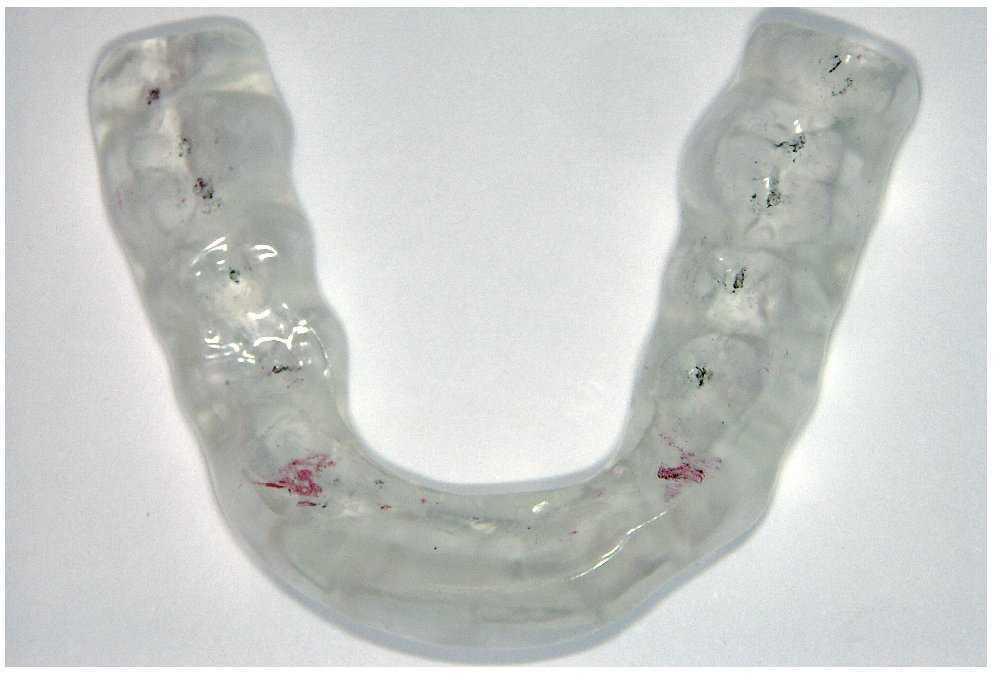

Antes de proceder al tratamiento definitivo de una pérdida de dimensión vertical con una prótesis se efectuará un aumento de la mordida provisional con una férula (fig. 6). Esto permite detectar precozmente los posibles problemas de adaptación que puedan surgir y eliminarlos introduciendo modificaciones en la férula. En casos excepcionales, el aumento de mordida provisional podrá mostrar que el paciente no tolera la elevación de la dimensión vertical. Esto da una idea de la necesidad del aumento de mordida provisional y reversible antes de realizar la rehabilitación definitiva con una prótesis.

Figura 6. Aumento de mordida provisional con una férula.